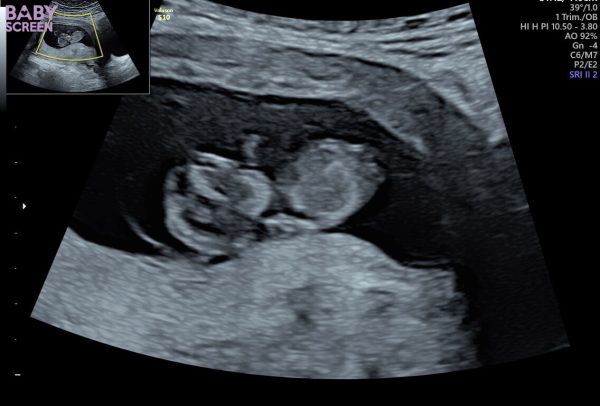

Idag gjorde Ida ett ultraljud. Lilla bebisen har allt ❤️ ett hjärta som slår, armar och ben och massor av energi. Eftersom inte barnets pappa vill ta del av sitt barn och uppleva allt det fantastiska kring graviditeten så ställer Idas bästa vän Diona upp med kärlek, glädje och inspiration ❤️

Beräknad förlossning är 19 maj nästa år ❤️ ser fram emot det!